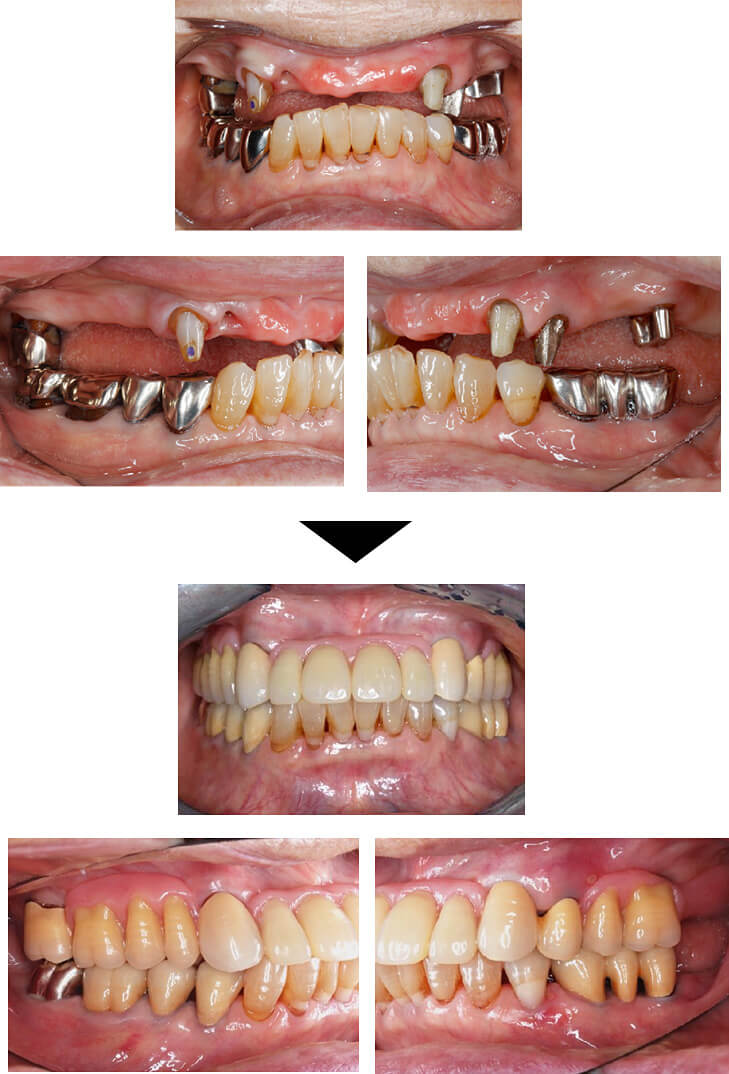

【75歳男性】

前歯のブリッジが外れ、噛めなくなってしまった方に対し、入れ歯を作成しました。一般的な入れ歯ではずれやすさや痛みが出ることもありますが、コーヌス義歯はフィット感に優れ、装着中の違和感が少ないです。

前歯部分にも金具が見えず、入れ歯とは気づかれにくい自然な見た目に仕上がりました。インプラントには抵抗があるという方でしたが、外科処置なしでしっかり噛めるようになりました。

| 主訴 | ブリッジが外れてしまい、全く噛めなくなった。 |

| 治療内容 | 上顎:コーヌス義歯(着脱式) 下顎:クラスプ(金具タイプ)義歯 |

| 治療期間 | 2年間 |

| 治療費 | 約3,000,000円(上下合計) |

| リスク・副作用 | ※予後を完全に保証する治療ではありません。 ※自由診療での治療です。 ※色調を合わせることが難しく、一度で色調が再現できないことがあります。再度色合わせが必要になるケースがあります。 ※精密な装置であるため、装置を落としたときに壊れやすいです。 |

【70歳男性】

入れ歯の不具合と虫歯のお悩みで来院された患者さまに、上顎にコーヌス義歯、下顎にはセラミッククラウンを用いた治療を行いました。

上顎には、見た目が自然で長く使える入れ歯を採用しました。前歯にも違和感なくなじみ、審美性の高さにご満足いただいています。下顎は歯周病や根の治療を丁寧に行ったうえで、セラミックによる修復を実施し、自然な仕上がりを実現しました。

| 主訴 | 入れ歯の不具合と虫歯を治したい。 |

| 治療内容 | 上顎:コーヌス義歯(着脱式) 下顎:セラミッククラウン |

| 治療費 | 約4,000,000円(上下合計) |

| リスク・副作用 | ※予後を完全に保証する治療ではありません。 ※自由診療での治療です。 ※色調を合わせることが難しく、一度で色調が再現できないことがあります。 ※再度色合わせが必要になるケースがあります。 ※精密な装置であるため装置が落としたときに破損するときがあります。 |